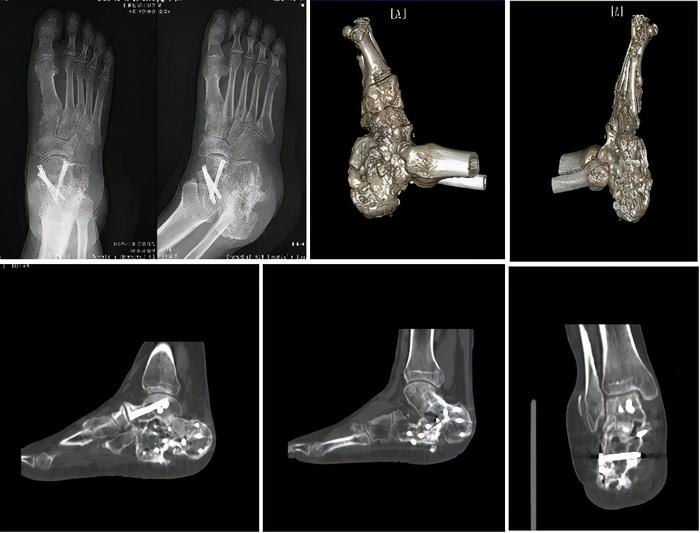

术前

现已术后两年,患者恢复良好,骨愈合良好,为取内固定再次到文根主任团队处就诊。根据患者病情,文根主任团队制定了详细手术计划,在取出内固定的同时行右跟骨区皮瓣修整,使局部皮肤更加美观。